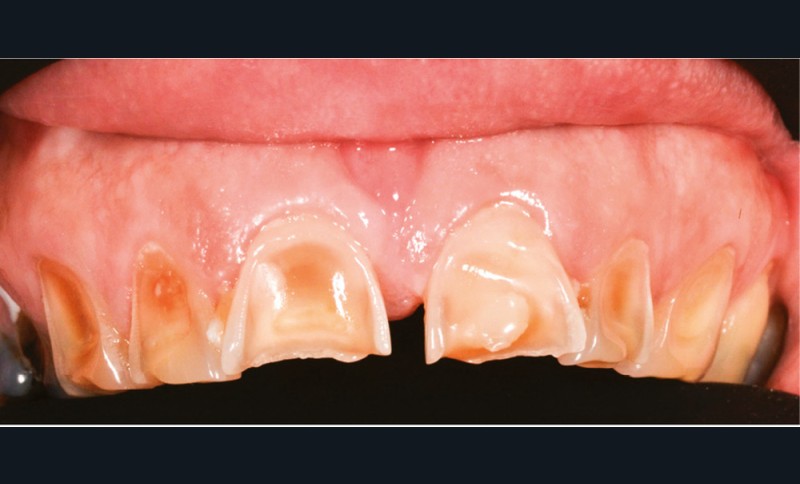

Lorsque l’on consulte les sites internet, il n’existe pas de consensus quant à la technique de son utilisation. Il est généralement conseillé de frotter du citron directement sur les dents (fig. 4), ou de tremper sa brosse à dents dans du jus de citron pur et d’effectuer son brossage. Certains « tutoriels » préconisent d’utiliser ce jus ou de l’eau citronnée comme bains de bouche ! Toutes ces stratégies pour « blanchir » les dents font appel à l’acide citrique contenu dans le citron. Cet acide est l’un des composants les plus présents dans les sodas et autres boissons acides. Si les consommateurs connaissent l’effet néfaste de ces boissons sur leurs dents, ils ne font malheureusement pas le rapprochement avec le citron, un fruit, forcément bon pour la santé. Malgré un grand nombre d’études démontrant les effets nocifs érosifs du citron sur les dents définitives comme sur les dents temporaires, ces pratiques continuent à être couramment utilisées [11].

Le processus d’érosion peut être divisé en deux étapes. La première est une déminéralisation partielle. À ce stade, une reminéralisation reste possible car de l’émail déminéralisé subsiste et des ions, calciums, phosphates ou du fluor, peuvent encore s’y fixer. Quand l’utilisation d’un acide devient trop fréquente par rapport aux processus de reminéralisation, les couches superficielles d’émail fragilisées à l’occasion de la première étape sont éliminées. La perte de substance est alors irréversible (fig. 5). Après la perte de l’émail, celle de la dentine sera plus rapide du fait de sa moindre minéralisation [12]. Ces lésions peuvent entraîner des sensibilités difficiles à éradiquer et créer un déficit esthétique, à l’opposé de l’effet recherché initialement. Les effets déminéralisants de l’acide citrique, rendraient la dent plus sensible aux lésions d’abrasion et d’attrition, augmentant d’autant plus la perte de substance [14].

Le biofilm qui se reforme en quelques minutes après le brossage, protège contre l’érosion en agissant comme une barrière de diffusion ou une membrane à perméabilité sélective limitant le contact direct entre et la surface de la dent et les acides [13]. L’action de frotter du citron ou d’en imbiber sa brosse à dents réduit ou supprime l’épaisseur de la pellicule, compromettant ainsi ses propriétés protectrices. Un brossage réalisé juste avant l’application d’acide citrique est donc délétère. Il en est de même immédiatement après, car cela va éliminer l’émail préalablement déminéralisé par le citron.